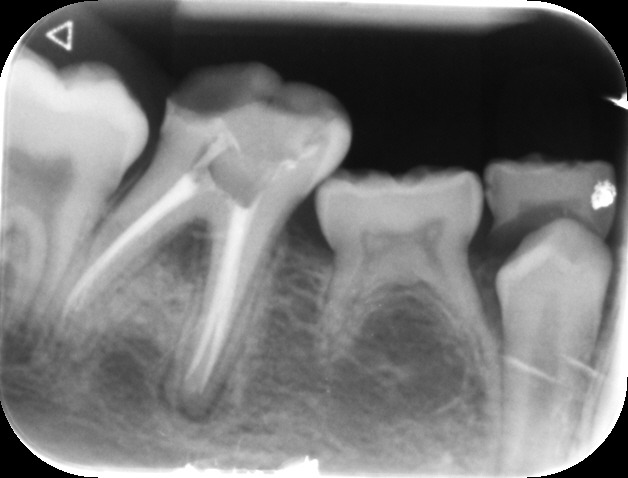

An access cavity is placed on the surface where the patient bites, to reach the root canals of the tooth. Once all the canals are identified, small files are used to remove the infected pulp.

Files of different sizes are used to eliminate bacteria and infection and to shape the canals. The canals are disinfected thoroughly with irrigants and later the canals will be sealed in 3 dimensions with a special medicament called gutta-percha to prevent reinfection of the tooth and the access cavity will be sealed with a temporary filling.